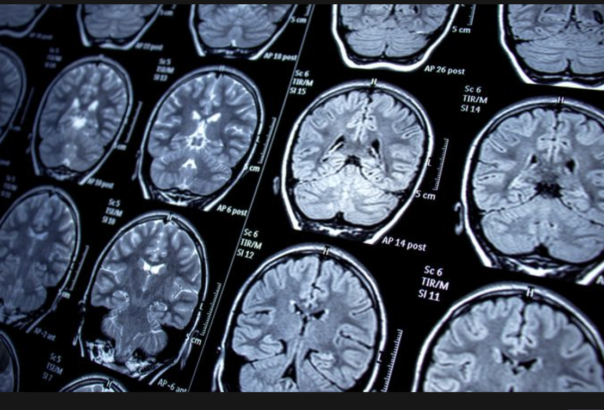

Covid 19 hayatımıza girdiğinden beri çoğu şey değişti ve özellikle uzun covid atlatanlarda bazı semptomlar ortaya çıktı. Trinity College Dublin’den bilim insanları ve FutureNeuro’dan araştırmacılardan oluşan bir ekip, uzun süreli COVID’li bazı hastalarda görülen beyin bulanıklığı ve bilişsel gerilemeyi anlamamız açısından derin öneme sahip büyük bir keşif duyurdu. Çalışma Nature Neuroscience’da yayınlandı. Yeni koronavirüs SARS-CoV2’nin 2019’un sonlarında ortaya çıkmasını takip eden aylarda, hastalar tarafından bildirilen ve uzun süreli Kovid olarak adlandırılan bir sendrom, akut enfeksiyonun kalıcı bir belirtisi olarak öne çıkmaya başladı.

Uzun süreli Kovidin bugüne kadar bildirilen 200’e kadar semptomu var, ancak genel olarak hastalar yorgunluk, nefes darlığı, hafıza ve düşünme sorunları ve eklem/kas ağrısı gibi kalıcı semptomlar bildirmekte. Tam iyileşme durumunda, enfeksiyondan sonra 12 haftadan fazla süren bu semptomlardan herhangi biri uzun süreli kovid olarak değerlendirilebilir. Uzun süreli kovid, pandeminin 2020’de patlak vermesinden bu yana artık önemli bir halk sağlığı sorunu haline geldi. Uluslararası görülme oranları farklılık gösterse de, SARS-CoV2 virüsü ile enfekte olan hastaların %10’a kadarını etkilediği tahmin edilmekte. COVID’de hastaların %50’sinden biraz azı bilişsel gerileme, yorgunluk ve bilinç bulanıklığı gibi bir tür kalıcı nörolojik etki bildirmekte.